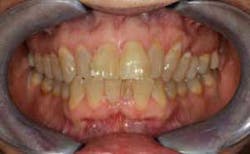

SFOT was used with a high-tech clear aligner to address hard- and soft-tissue deficiencies and severe maxillary and mandibular arch constriction.

A healthy, 57-year-old female presented with a lifelong desire for healthy, straight teeth and a beautiful smile. She had been told numerous times that it was not possible without premolar extractions.

SFOT surgery was performed in the maxillary and mandibular arches with deep buccal corticotomies. Particulate, demineralized, freeze-dried bone allograft and acellular dermal matrix were used to augment the ridges.

Total treatment time: 6 months. Patient declined recommended further clear aligner refinement and fine-tuning periodontal plastic surgery.